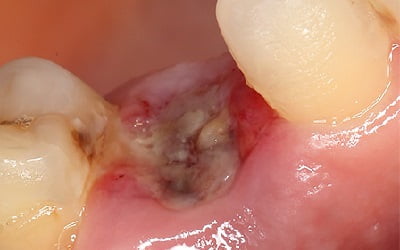

Альвеолит: фото

Фото, сделанные стоматологами, демонстрируют, что альвеолит выглядит как пустая лунка, в которой находятся остатки пищи и частички отмерших тканей. В то время как в лунке, заживающей без осложнений, можно увидеть темно-красный кровяной сгусток.